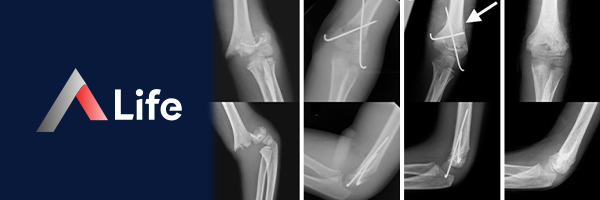

Suprakondiler Humerus Kırığı​

Suprakondiler humerus kırığı, dirsek ekleminin hemen üzerinde, humerus kemiğinin (kol kemiği) alt ucunda meydana gelen bir kırıktır. Bu kırık tipi, çoğunlukla çocuklarda görülür ve genellikle avuç içi açık şekilde düşme sonucu oluşur.

suprakondiler_humerus_k__r__________634d60bd.webp

Humerus Alt Uç Kırığı​

Humerus alt uç kırığı, kol kemiğinin dirsek eklemine yakın olan alt kısmında meydana gelen kırıklardır. Bu kırıklar, genellikle düşme, trafik kazaları veya spor yaralanmaları gibi travmalar sonucu oluşur. Çocuklarda ve yaşlılarda daha sık görülür.

Humerus alt uç kırıkları, kırık çizgisinin yerine ve eklem yüzeyinin tutulumuna göre farklı tiplerde sınıflandırılır.

• Ekstraartiküler Kırıklar: Eklem yüzeyini içermeyen kırıklardır.

• Suprakondiler Kırık: Dirsek ekleminin hemen üzerinde meydana gelir. Çocuklarda en sık görülen humerus kırığı tipidir.

• Epikondil Kırığı: Humerus kemiğinin alt ucundaki medial veya lateral epikondilin kırılmasıdır.

• İntraartiküler Kırıklar: Eklem yüzeyini içeren kırıklardır.

• Kapitulum Kırığı: Humerus kemiğinin alt ucunda, radius kemiği ile eklem yapan kapitulumun kırılmasıdır.

• Troklea Kırığı: Humerus kemiğinin alt ucunda, ulna kemiği ile eklem yapan trokleanın kırılmasıdır.

Humerus alt uç kırıkları tedavisi, kırığın türüne, yerine, şiddetine ve hastanın yaşına ve genel sağlık durumuna bağlı olarak değişir.

• Konservatif Tedavi:

• Alçı: Kırık kemik uçları yerinden oynamamışsa, alçı ile tedavi edilebilir.

• Fizik Tedavi: İyileşme sürecinde, dirseğin hareketliliğini ve gücünü geri kazanmak için fizik tedavi uygulanır.

• Cerrahi Tedavi:

• Kapalı Redüksiyon ve Perkütan Pinleme: Kırık parçaları yerinden oynamışsa, kapalı yöntemle yerine oturtulup tellerle sabitlenebilir.

• Açık Redüksiyon ve İç Fiksasyon: Daha karmaşık kırıklarda, açık cerrahi ile kırık parçaları yerine oturtulup plakalar ve vidalarla sabitlenir.

• Dirsek Protezi: Çok parçalı kırıklarda veya yaşlı hastalarda, dirsek eklemi protezi uygulanabilir.